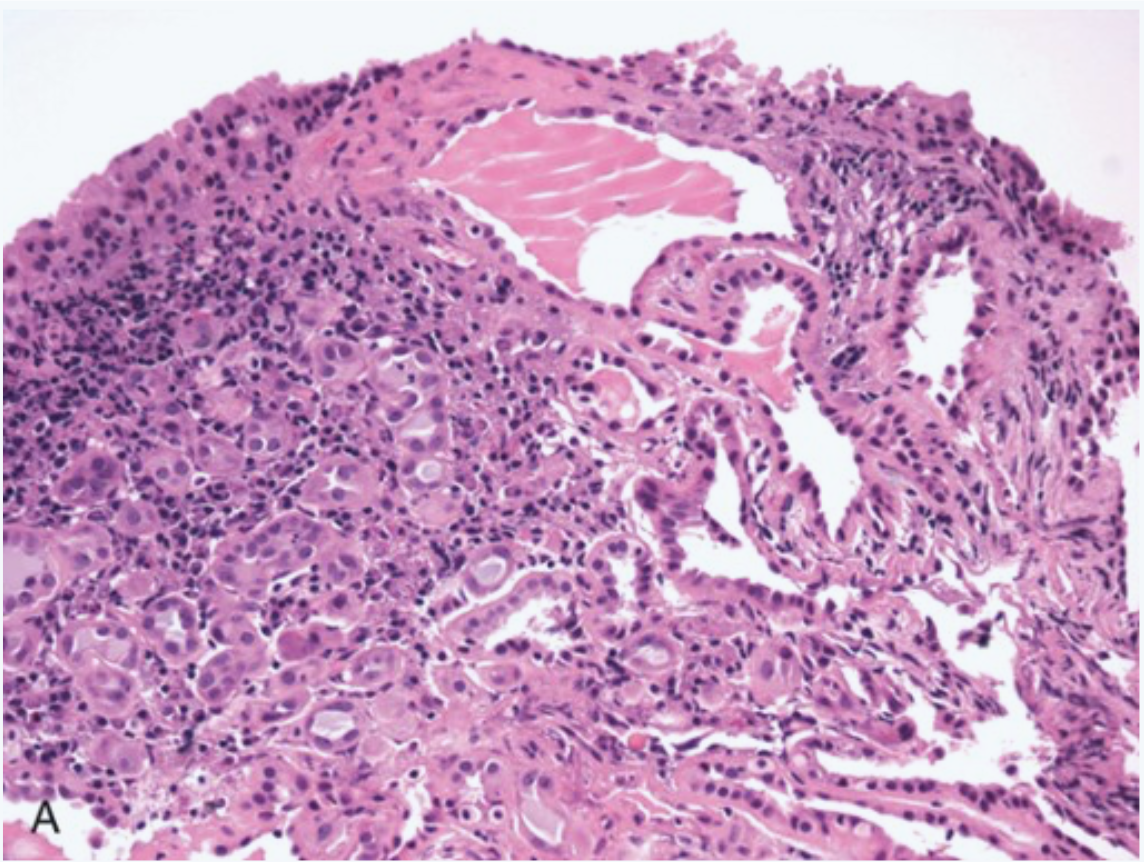

Posterior bladder wall, young man, post UTI (Trauma, calculi, transplant)

Nephrogenic adenoma.

SMALL TUBULES RESEMBLING RENAL TUBULES

Proliferation of small tubules or papillary fronds or flat architecture- all lined by eosinophilic cuboidal epithelium.

USUALLY RESTRICTED TO SUP LP BUT CAN BE INFILTRATIVE

No mitotic activity or nuclear pleomorphism

Variable mixed inflammation